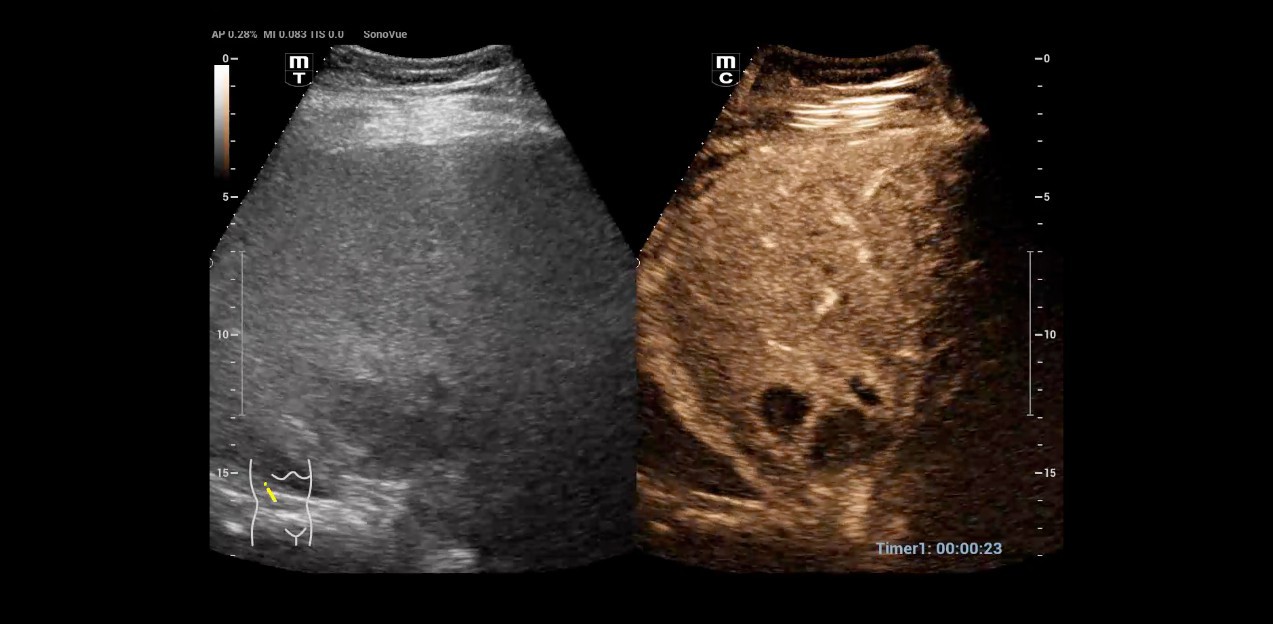

Dr. Seibel chose Resona I9 for various reasons. First, the high-end device offers excellent image quality with high resolution, as well as focused examination techniques that facilitate diagnosis. For instance, he frequently uses contrast-enhanced ultrasound (CEUS) to clarify uncertain findings.